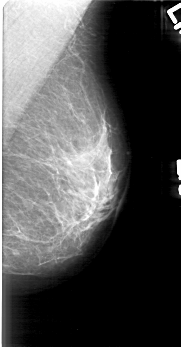

ics_version 1.0 filename D-4166-1 DATE_OF_STUDY 12 6 1997 PATIENT_AGE 44 FILM FILM_TYPE REGULAR DENSITY 2 DATE_DIGITIZED 2 6 1999 DIGITIZER HOWTEK 43.5 SEQUENCE LEFT_CC LINES 5371 PIXELS_PER_LINE 2671 BITS_PER_PIXEL 12 RESOLUTION 43.5 NON_OVERLAY LEFT_MLO LINES 5191 PIXELS_PER_LINE 2701 BITS_PER_PIXEL 12 RESOLUTION 43.5 NON_OVERLAY RIGHT_CC LINES 4786 PIXELS_PER_LINE 2416 BITS_PER_PIXEL 12 RESOLUTION 43.5 OVERLAY RIGHT_MLO LINES 4906 PIXELS_PER_LINE 2836 BITS_PER_PIXEL 12 RESOLUTION 43.5 OVERLAY |

FILE: D_4166_1.RIGHT_CC.OVERLAY TOTAL_ABNORMALITIES 1 ABNORMALITY 1 LESION_TYPE CALCIFICATION TYPE AMORPHOUS DISTRIBUTION CLUSTERED ASSESSMENT 0 SUBTLETY 2 PATHOLOGY BENIGN TOTAL_OUTLINES 1 BOUNDARY |